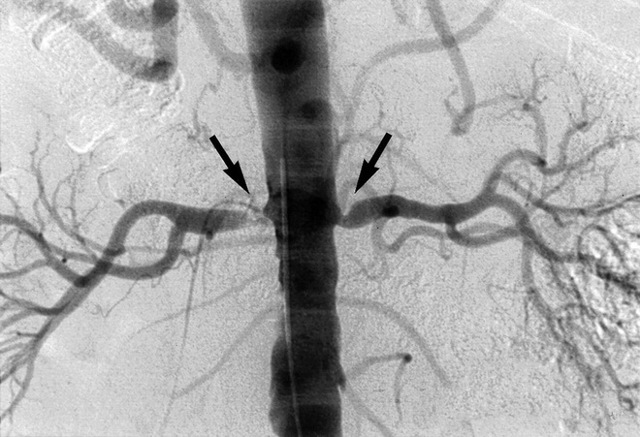

Реноваскулярной гипертензией, или РВГ, называют форму артериальной гипертензии, которая обусловлена сужением артерий почек или их крупных ветвей. Поражение может быть как односторонним, так и двусторонним (стеноз правой и левой артерий). По статистике, РВГ составляет от двух до пяти процентов от всех артериальных гипертензий и около 10 % от всех почечных гипертензий.

При одностороннем стенозе почечных артерий с помощью рентгенографии, УЗИ и томографии определяют, что одна почка меньше другой по размеру. Экскреторная урография, кроме разницы в размере, может обнаружить нарушение выделительной функции почки.

Наиболее достоверным методом диагностики РВГ считается ангиография почечных артерий. С ее помощью можно определить происхождение патологического процесса, локализацию стеноза и его степень, что очень важно при вынесении решения о хирургическом вмешательстве.